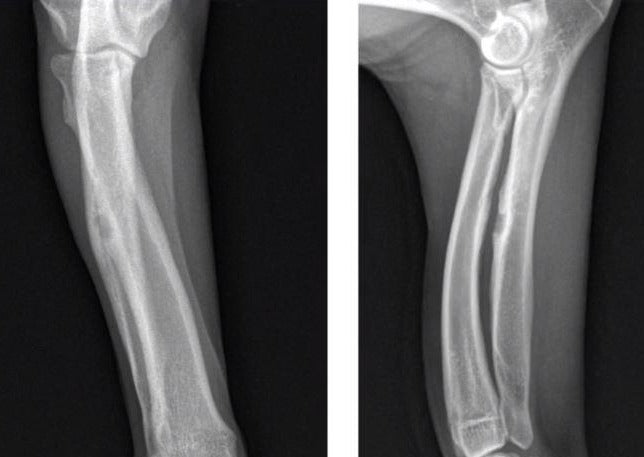

Das „Lesen von Röntgenbildern“ ist ein fehleranfälliger Prozess. Strukturierte Ausbildung, gezieltes Training und kontinuierliche Übung durch Spezialisierung sowie lebenslange Fortbildung helfen uns, unsere Fehlerquote reduzieren. Fehler sind unvermeidlich. Wer arbeitet, macht Fehler. Wer viel arbeitet macht viele Fehler. Die Akzeptanz dieser Tatsachen reduziert die Angst vor Fehlern und erlaubt es uns, sich mit unseren Fehlern auseinander zu setzen und daraus sinnvoll zu lernen. Die Kenntnis häufiger und typischer Fehler ermöglicht es uns, Fehlerquellen zu identifizieren und Fehler im Vorfeld zu vermeiden. Die wichtigsten und häufigsten Fehler beim „Lesen von Röntgenbildern“ sowie sinnvolle Vermeidungsstrategien werden im Rahmen des Vortrages erörtert.